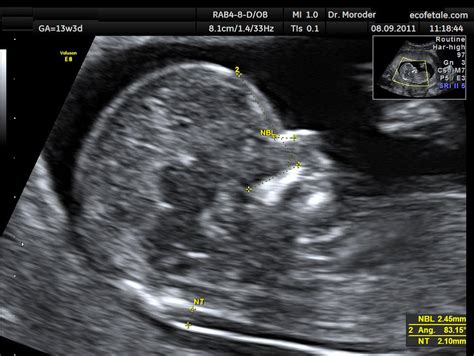

- Screening del primo trimestre (Bi-test): Eseguito attorno alla 12ª settimana, combina il dosaggio di proteine (free-beta hCG e PAPP-A) con l'ecografia per la misurazione della translucenza nucale (lo spessore di uno spazio liquido alla nuca del feto).

- NIPT Test (Non-Invasive Prenatal Test): Ricerca il DNA fetale libero nel sangue materno. Disponibile dalla 10ª settimana, offre sensibilità e specificità vicine al 100%, pur rimanendo un test di screening che, in caso di positività, richiede conferma tramite esami invasivi.

- Diagnostica invasiva: L'amniocentesi (15ª-19ª settimana) e la villocentesi (9ª-11ª settimana) permettono di analizzare direttamente il corredo cromosomico fetale. La cordonocentesi, invece, è un prelievo di sangue fetale praticato dopo la 18ª settimana.